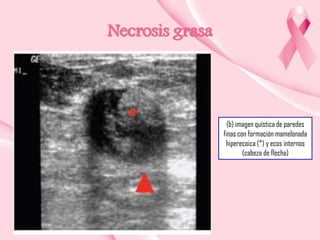

Necrosis grasa

(b) imagen quística de paredes

finas con formación mamelonada

hiperecoica (*) y ecos internos

(cabeza de flecha)